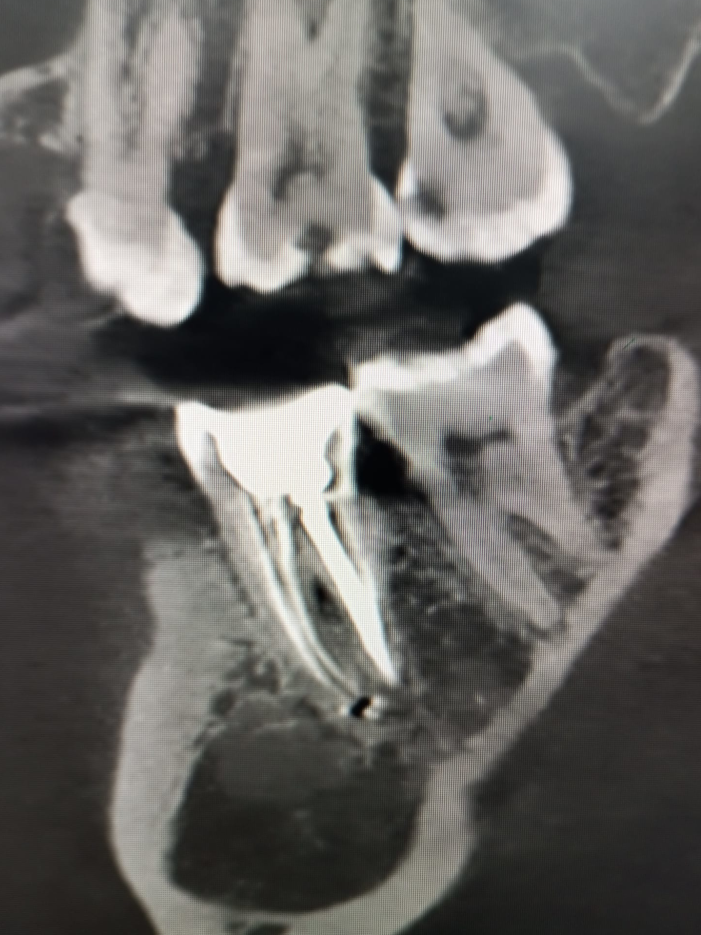

Galería

Algunos de nuestros tratamientos de endodoncia que permiten salvar piezas dentales, eliminar infecciones y devolver la salud y funcionalidad a tu sonrisa.